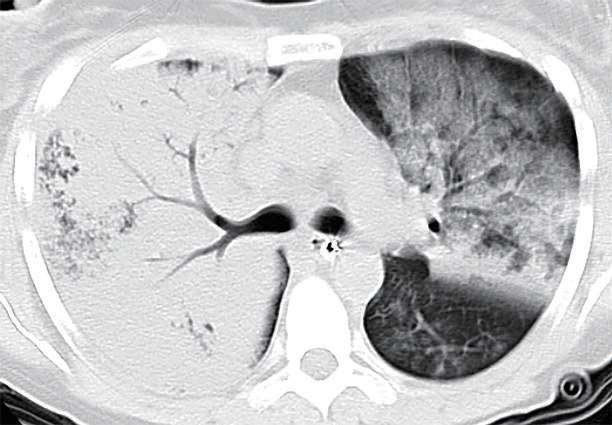

3.肺部感染: 肺部感染的病因多样,可能是细菌、病毒、真菌或其他微生物引起的。有些重症肺炎,如大家熟悉的“白肺”,通过支气管镜获取下呼吸道分泌物进行涂片、培养或分子生物学检测,可以帮助医生准确判断感染的具体病原体,从而指导针对性的抗生素或抗病毒治疗,避免盲目用药。对于某些难以自行咳出痰液的患者,尤其是那些咳嗽反射弱、免疫力低下或有吸入性肺炎风险的人群,支气管镜可以直接进入气道,清除深部的痰液和分泌物,减少感染负荷,促进病情好转。

双肺肺炎,双肺图像就像大家熟悉的“白肺”。左肺呈大片实变,右肺为大量磨玻璃渗出影